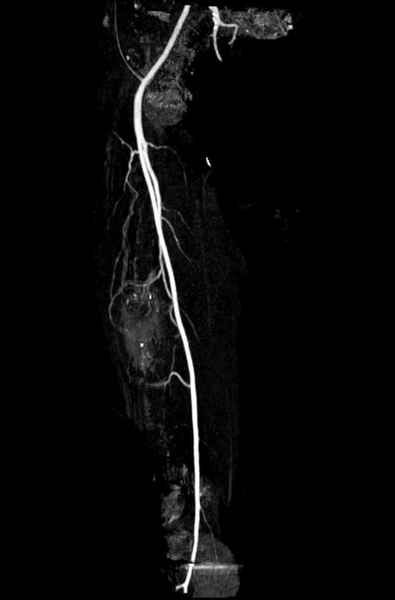

Со слов, больная ничем не болела, только последние 3 месяцев чувствовала боли в бедренной области. КТ брюшной полости подтвердил увеличенную правую почку. (5-6)

Для предупреждения кровотечения во время рассверливания, за день до операции провели эмболизацию сосудов питающий метастаз. http://radiology.rsnajnls.org/cgi/reprint/150/3/673.pdf (7-11, 12-15-16)